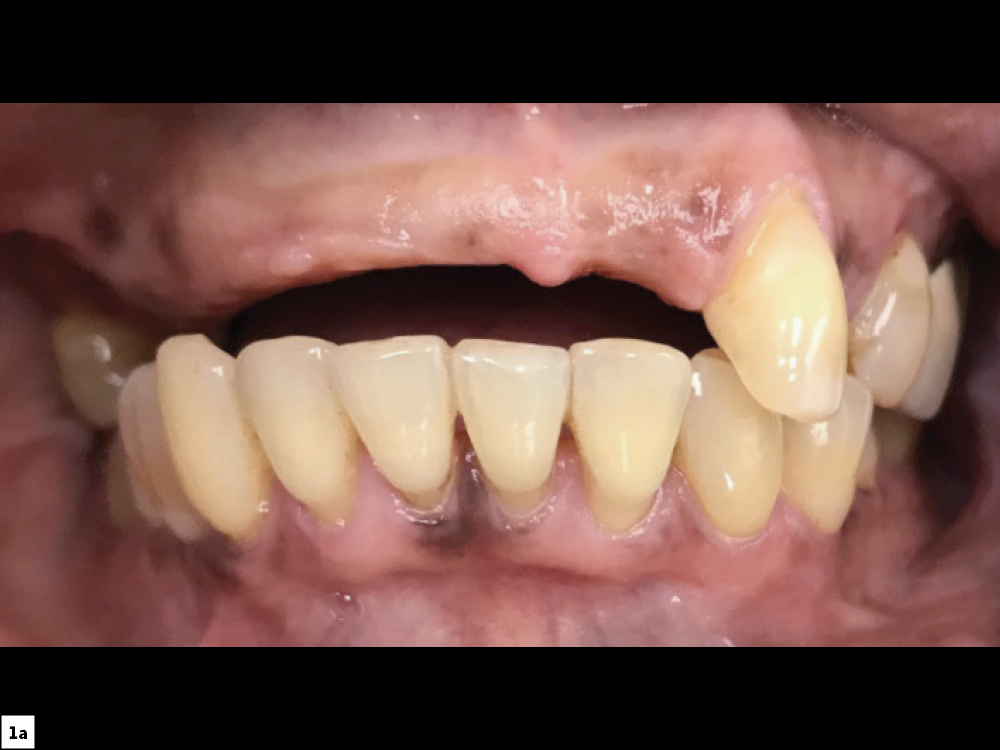

Figures 1a, 1b: At the initial consultation, the patient complained of her removable partial denture, desiring a fixed restoration that looked and felt more like natural teeth and would allow her to eat normally and smile without worrying about her prosthesis becoming loose. Because the patient’s remaining teeth were healthy and a conventional bridge was not an option, the patient agreed to receive four implants to support an FP-3 prosthesis, which would replace the missing teeth as well as the lost hard and soft tissue in the edentulous span.